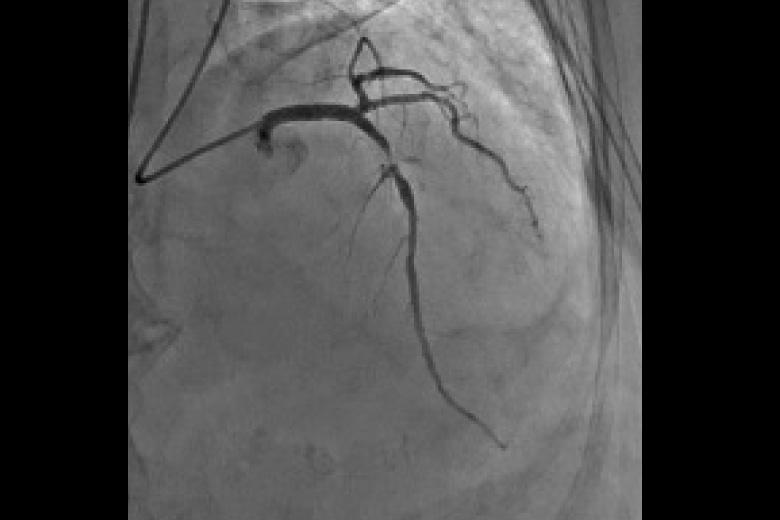

血管の中に造影剤を注入して脳、心臓、肝・胆道・膵、腎、四肢などの血管を造影診断、治療します。 心臓を中心とし検査を行う装置と腹部を中心とした検査をおこなう装置(IVR-CT)にて検査、治療をおこなっております。 心臓検査ではバイプレーン(2管球)装置のため少ない造影剤で検査を受けることができます。また腹部装置は80列CTとの組み合わせのためより高精細な画像が収集でき3Dガイド下にて検査・治療を行っています。

心臓用アンギオ装置 INFINIX Celeve I

冠動脈狭窄 治療前

冠動脈狭窄 治療後